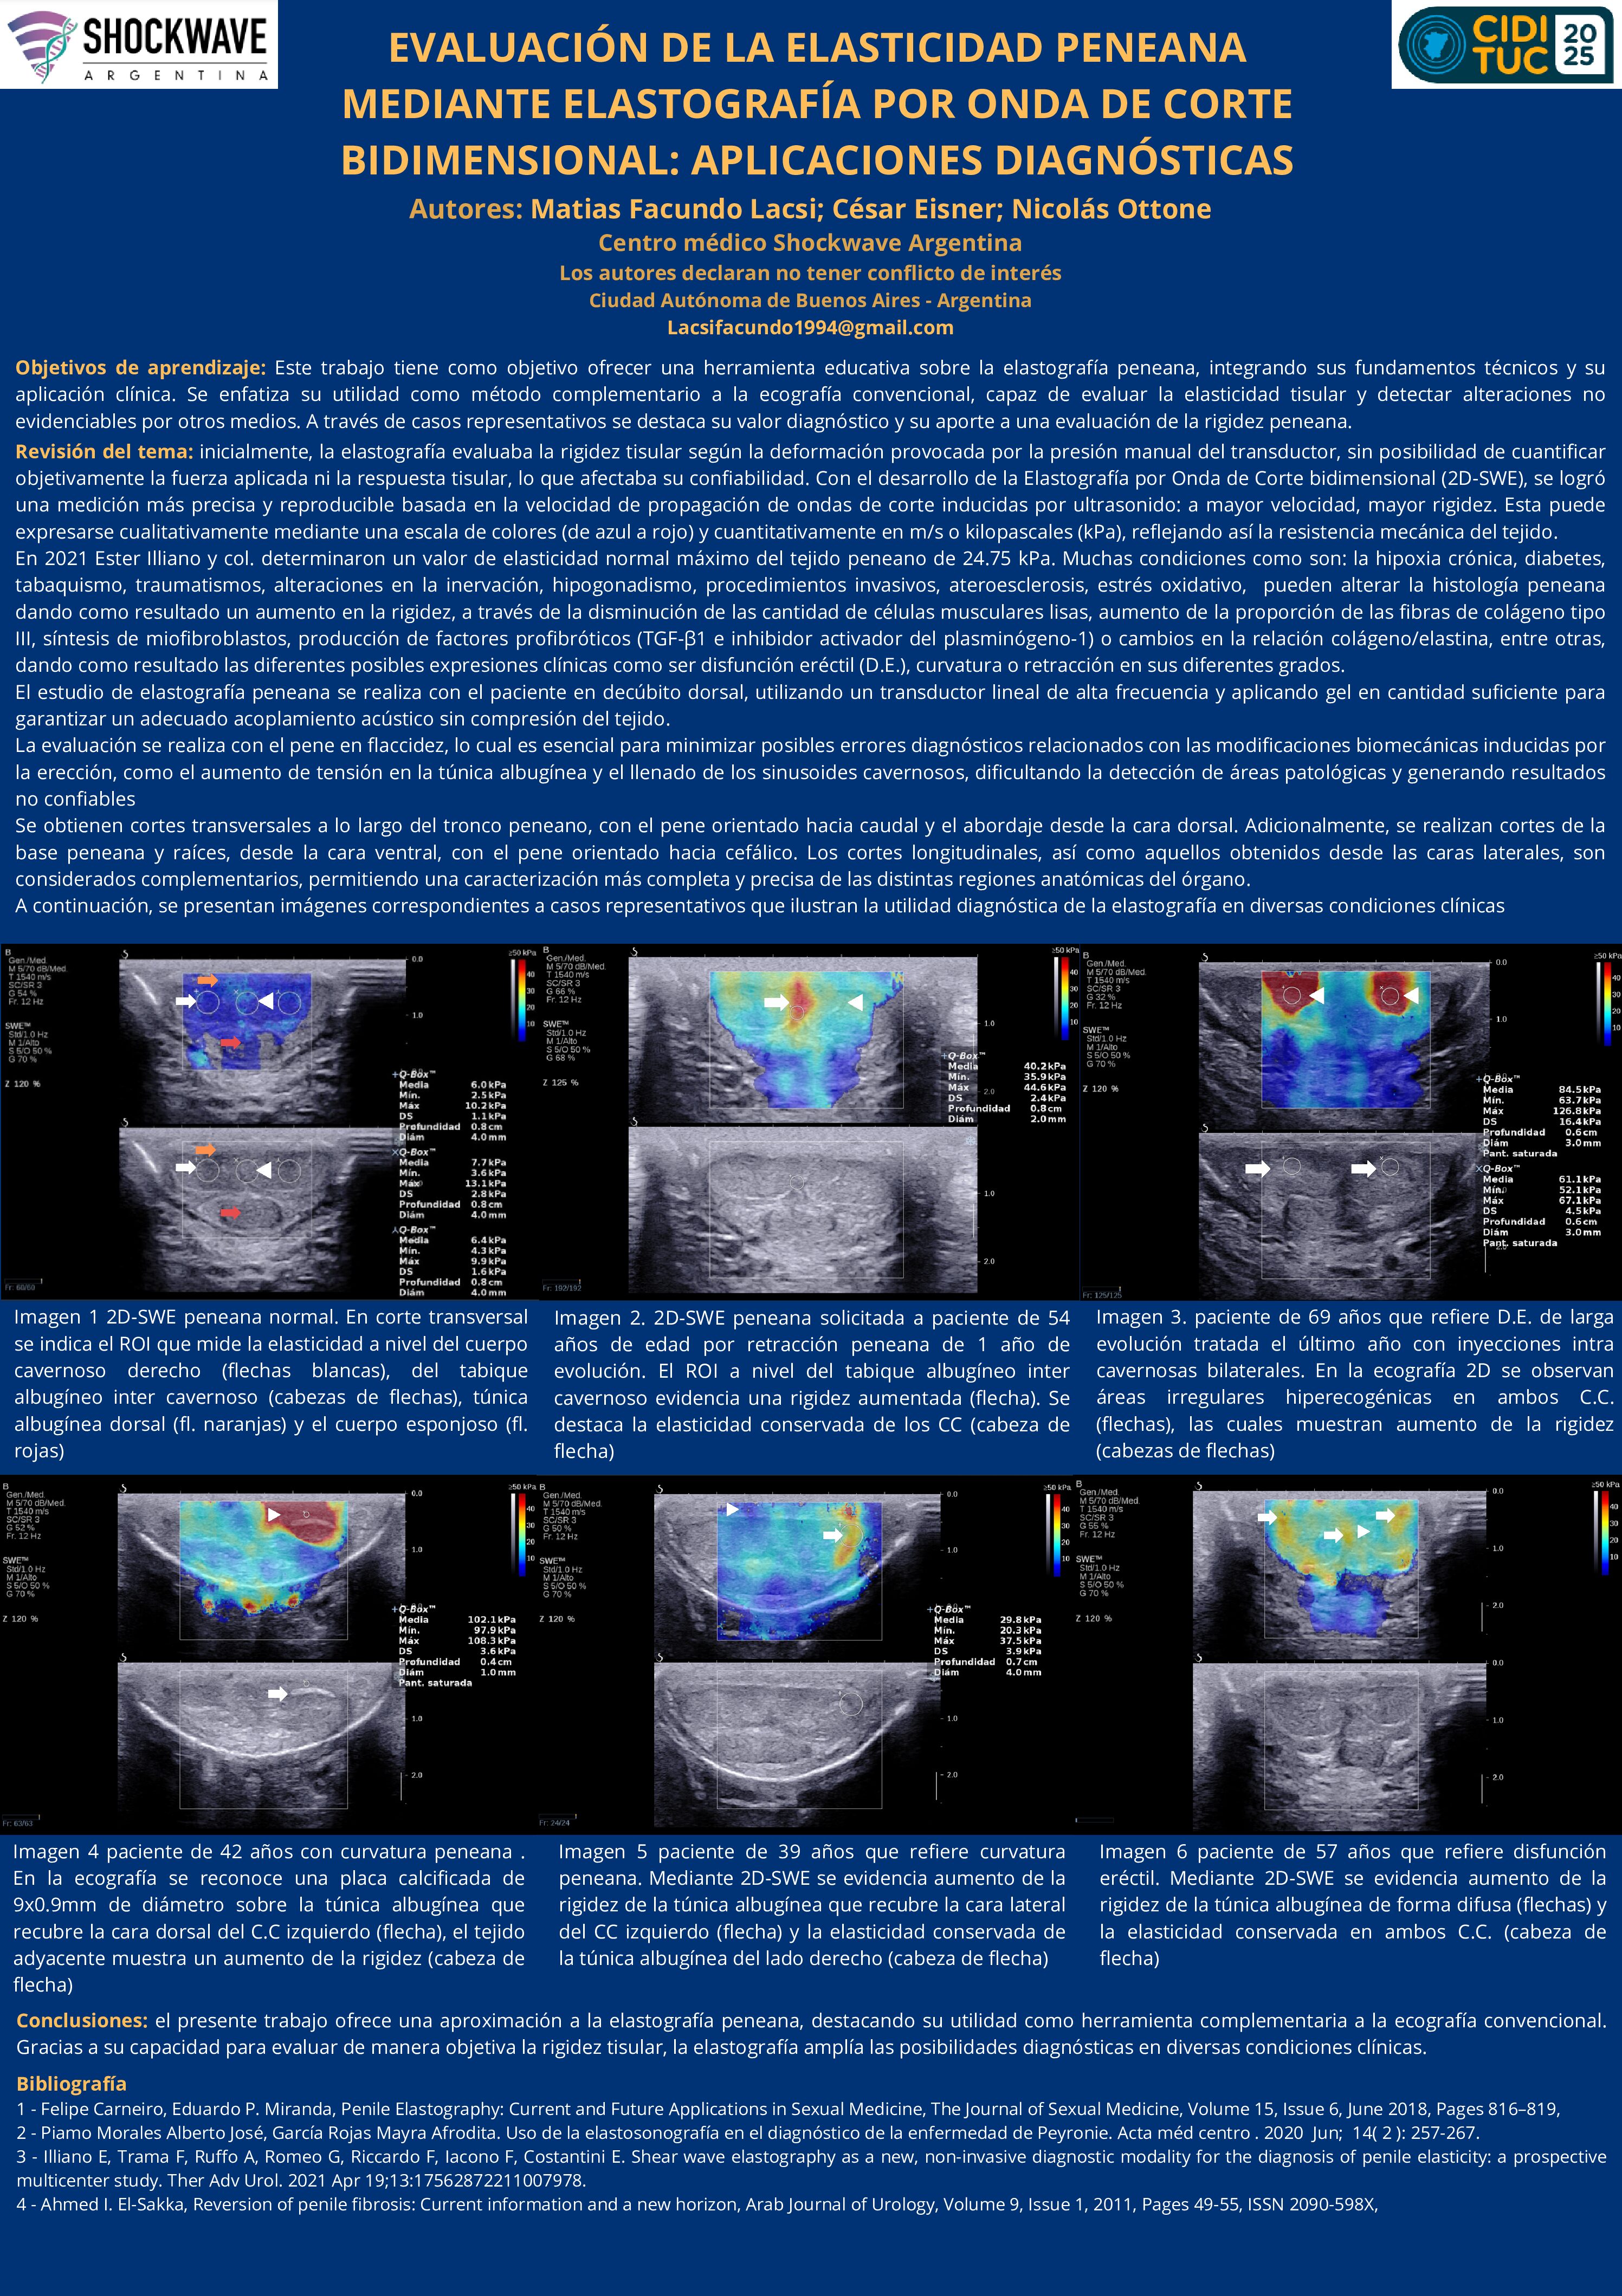

EVALUACIÓN DE LA ELASTICIDAD PENEANA MEDIANTE ELASTOGRAFÍA POR ONDA DE CORTE BIDIMENSIONAL: APLICACIONES DIAGNÓSTICAS

07/07/2025